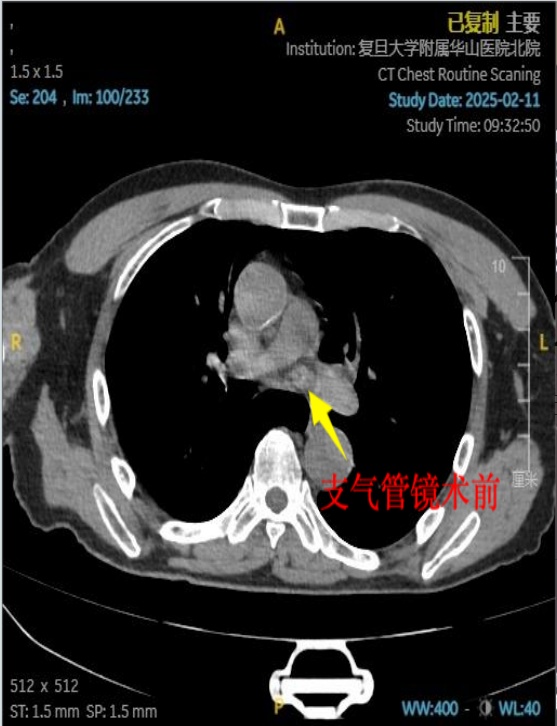

接诊的华山医院宝山院区呼吸与危重症医学科副主任医师杨海华介绍:“患者的虾是在左侧支气管里面,整个左侧主支气管被完全阻塞,无法通气,导致患者出现严重缺氧状态。当时我们给他测的氧饱和度只有85%,血气分析显示氧合指数只有157,属于Ⅰ型呼吸衰竭的情况。”

医护团队立即为蔡老伯安排支气管镜取出异物。然而由于虾体有小拇指大小,虾壳表面光滑,虾肉部分因煮熟后质地松软,再加上虾头的虾枪部位尖锐锋利,取出过程中极易划伤气道黏膜,这些都给夹取带来了不小难度。最终,经过半个多小时的紧张手术,整只河虾被成功取出,老人呼吸困难的症状马上缓解。“非常感谢医护人员,因为这条命是他们救回来的!”老人感激地说。